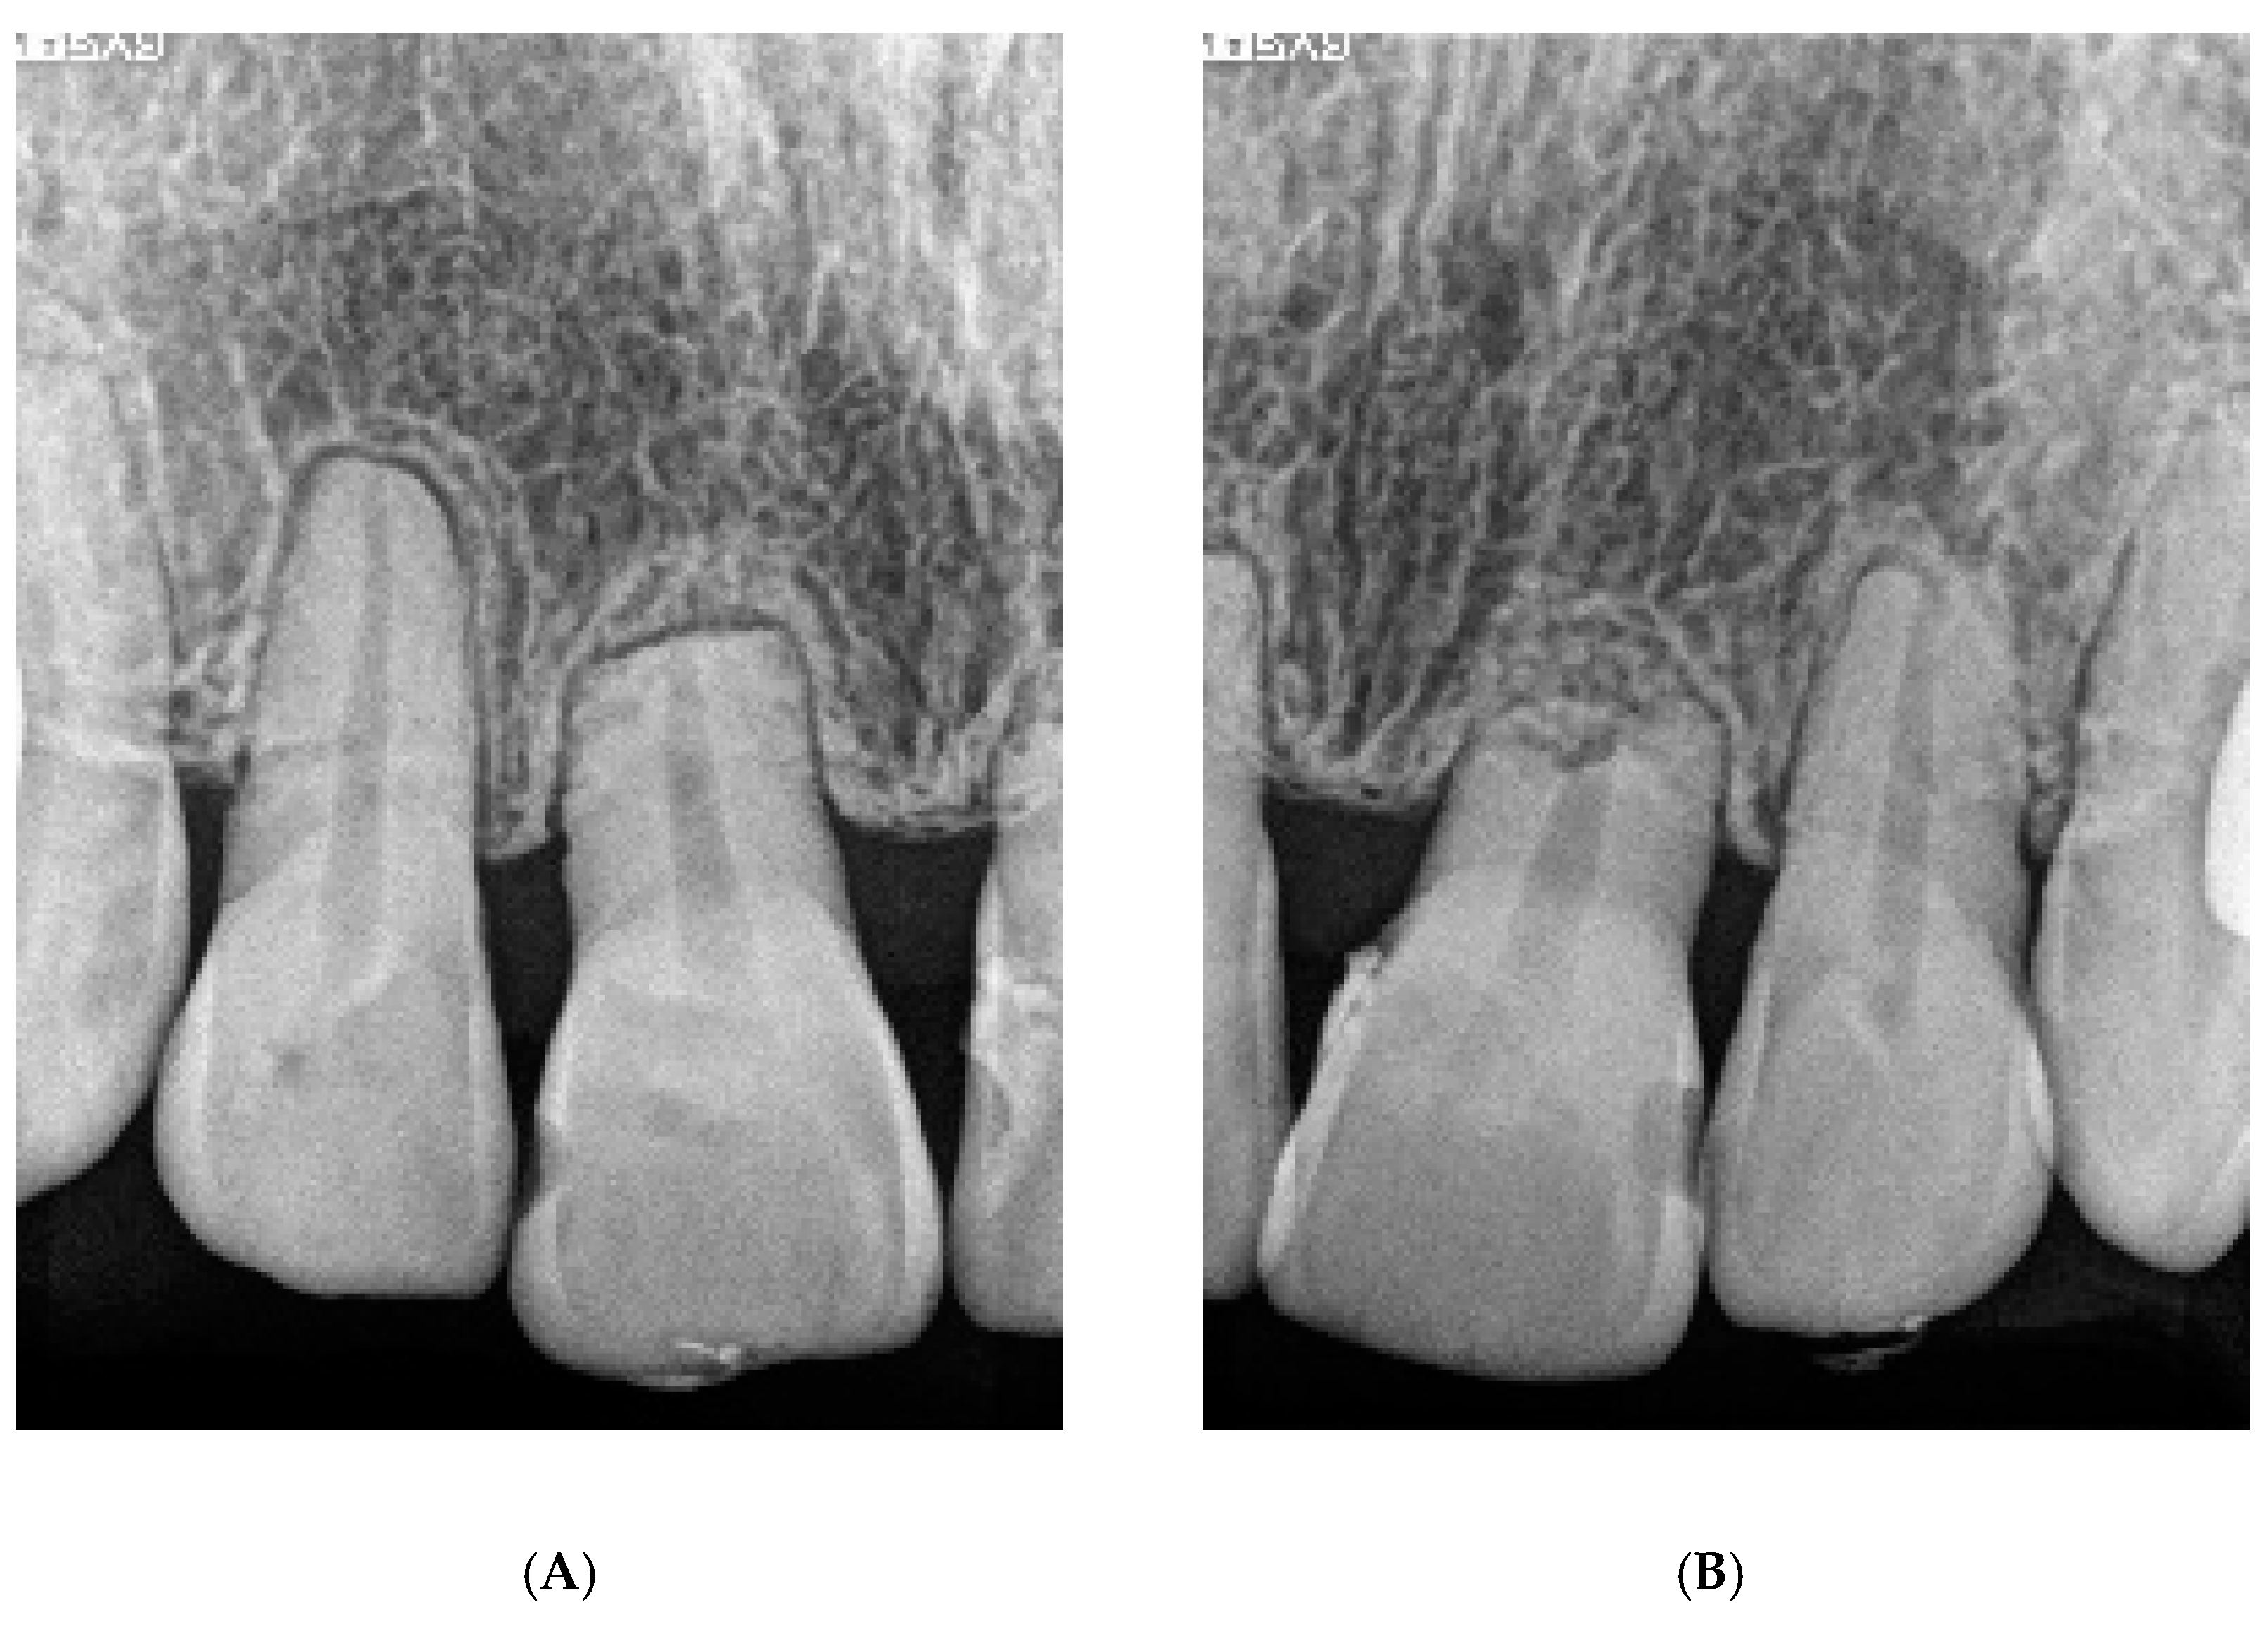

6.1. Diagnosis

6.4. Treatment Progress

6.5. Treatment Results

6.6. Case Summary